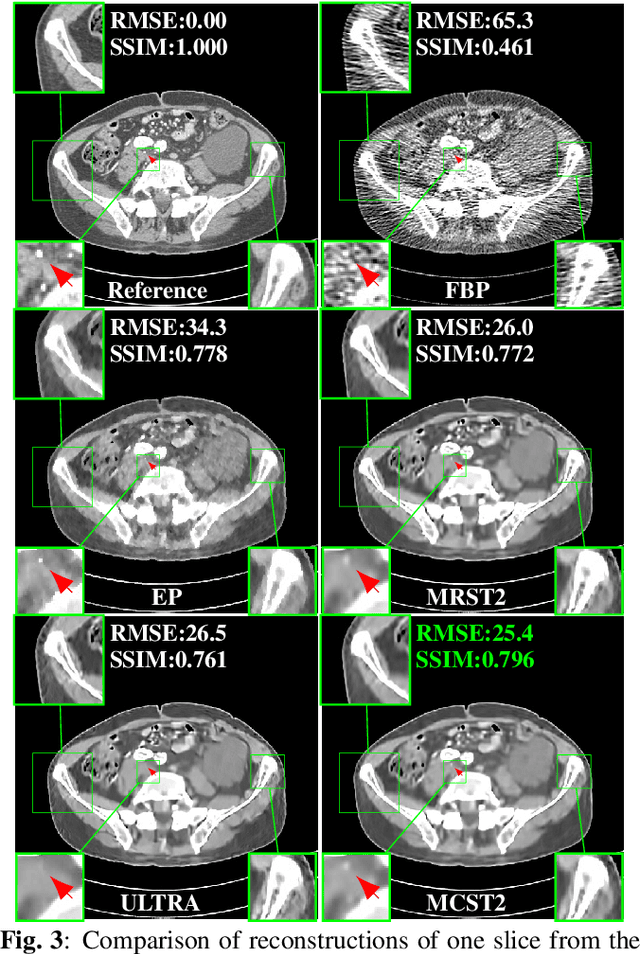

Achieving high-quality reconstructions from low-dose computed tomography (LDCT) measurements is of much importance in clinical settings. Model-based image reconstruction methods have been proven to be effective in removing artifacts in LDCT. In this work, we propose an approach to learn a rich two-layer clustering-based sparsifying transform model (MCST2), where image patches and their subsequent feature maps (filter residuals) are clustered into groups with different learned sparsifying filters per group. We investigate a penalized weighted least squares (PWLS) approach for LDCT reconstruction incorporating learned MCST2 priors. Experimental results show the superior performance of the proposed PWLS-MCST2 approach compared to other related recent schemes.